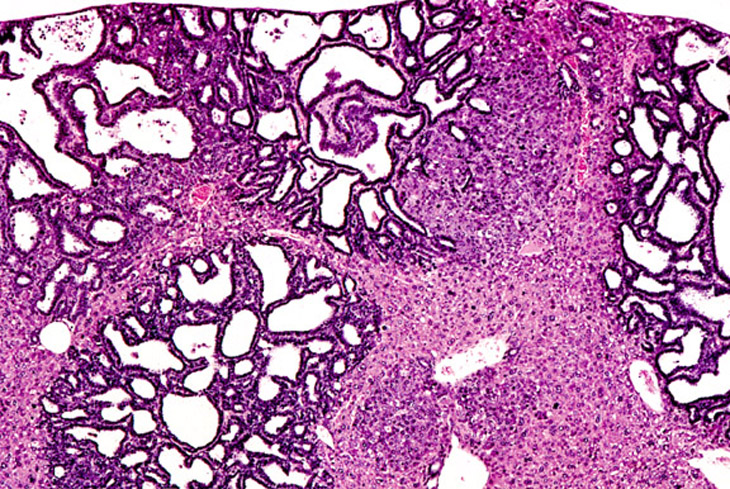

Multiple biliary and hepatocellular hyperplastic and neoplastic lesions in the liver of a 4-week-old transgenic mouse.